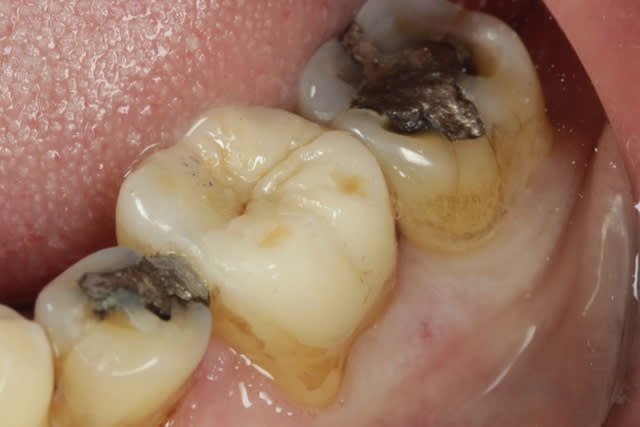

Face vestibulaire pas alignés, différence de niveau vertical des crétes marginal, clairement un traitement ODF s'impose.

Sinon ça semble une très bonne indication pour des tenons dentinaire.

Je commencerais par enlever le morceau de salade coincée entre la 6 et la 7 :-)

Sinon, ça serait bien d'avoir une rétro...

C'est un cas limite.

Mais le risque c'est de se retrouver a devoir dépulper et faire une couronne, alors pourquoi le faire tout de suite.

Sur cette dent, où 3/4 est à plat et quasiment au niveau du collet, si tu taille le reste il reste rien.

Tu peux faire un moignon en compo pour ton esprit mais il sera pas moins collé que tout le reste. Donc si on colle on garde ce qu'on peut...

Tailler plus pour coller tout à plat, j'arrive pas à comprendre l’intérêt. Moins d'émail, marge plus basse, stabilisation 0, proximité pulpaire plus importante.